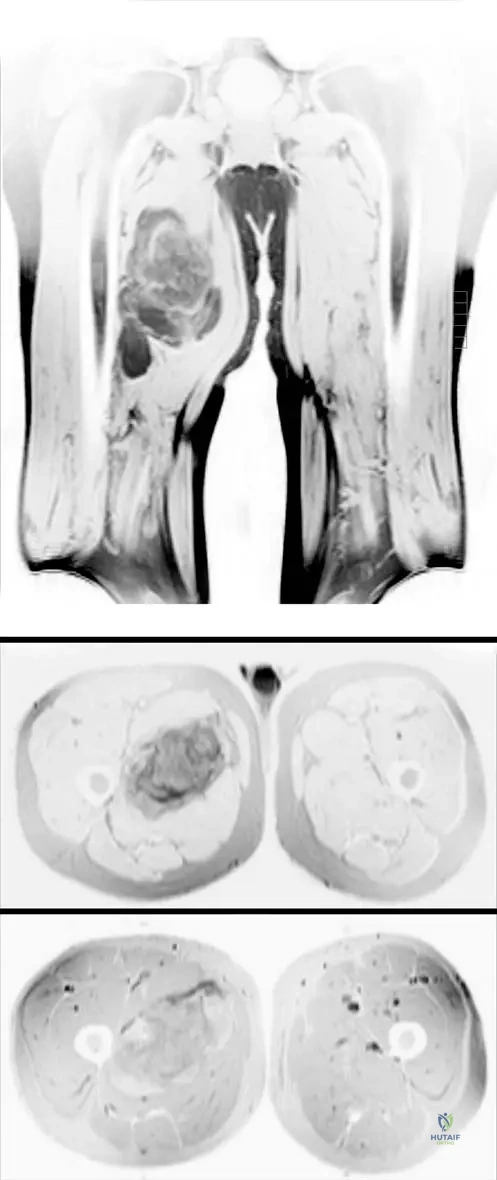

A 13-year-old male presents with a painful, rapidly growing mass in his distal femur. MRI images are obtained, as shown. These images demonstrate a large heterogeneous destructive mass in the bone with a large associated soft tissue mass. What is the most likely diagnosis based on these typical findings?

View Answer & Explanation

Correct Answer: C

Rationale: The clinical context for Fig. 8.66 explicitly states these MRI images "show typical findings of an osteosarcoma. There is a large heterogeneous destructive mass in the bone with a large associated soft tissue mass." This is a classic presentation for osteosarcoma in this age group. Chondrosarcoma typically presents with chondroid matrix, Ewing sarcoma with a permeative pattern and onion-skin periosteal reaction, osteochondroma is a benign exostosis, and fibrous dysplasia is a benign fibrous lesion.

A 14-year-old male is diagnosed with a conventional osteosarcoma of the distal femur. Following initial radiographs and CT, the orthopedic oncologist orders an MRI of the entire femur. What is the MOST critical information this MRI is intended to provide?

Rationale: MRI is the most accurate imaging tool for determining the intraosseous and extraosseous extent of the tumor. It is also important to image the entire bone involved with osteosarcoma to evaluate for skip metastasis. This information is crucial for surgical planning and determining resection margins. Confirming osteoid matrix is done by biopsy. Assessing mineralization is better with CT. Pulmonary metastases are evaluated with chest CT. Differentiating benign from malignant is usually achieved with initial radiographs and biopsy. The image (Fig. 8.66 a–c) shows how MRI clearly delineates the extent of the mass.